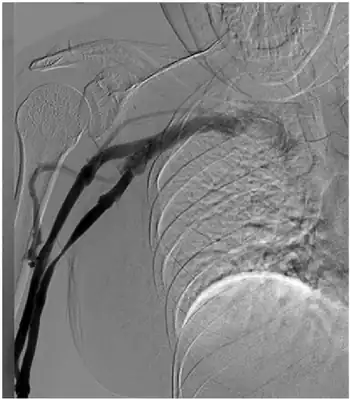

Findings consistent with pectoralis minor syndrome on the right side